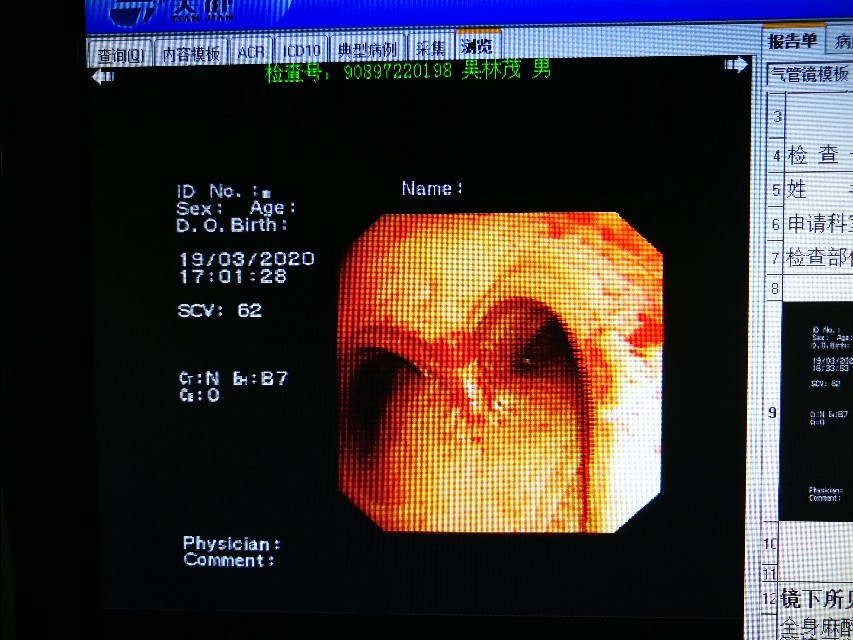

气管镜下可以更直观的看到气管到底多狭窄。只剩下几毫米的小孔了。